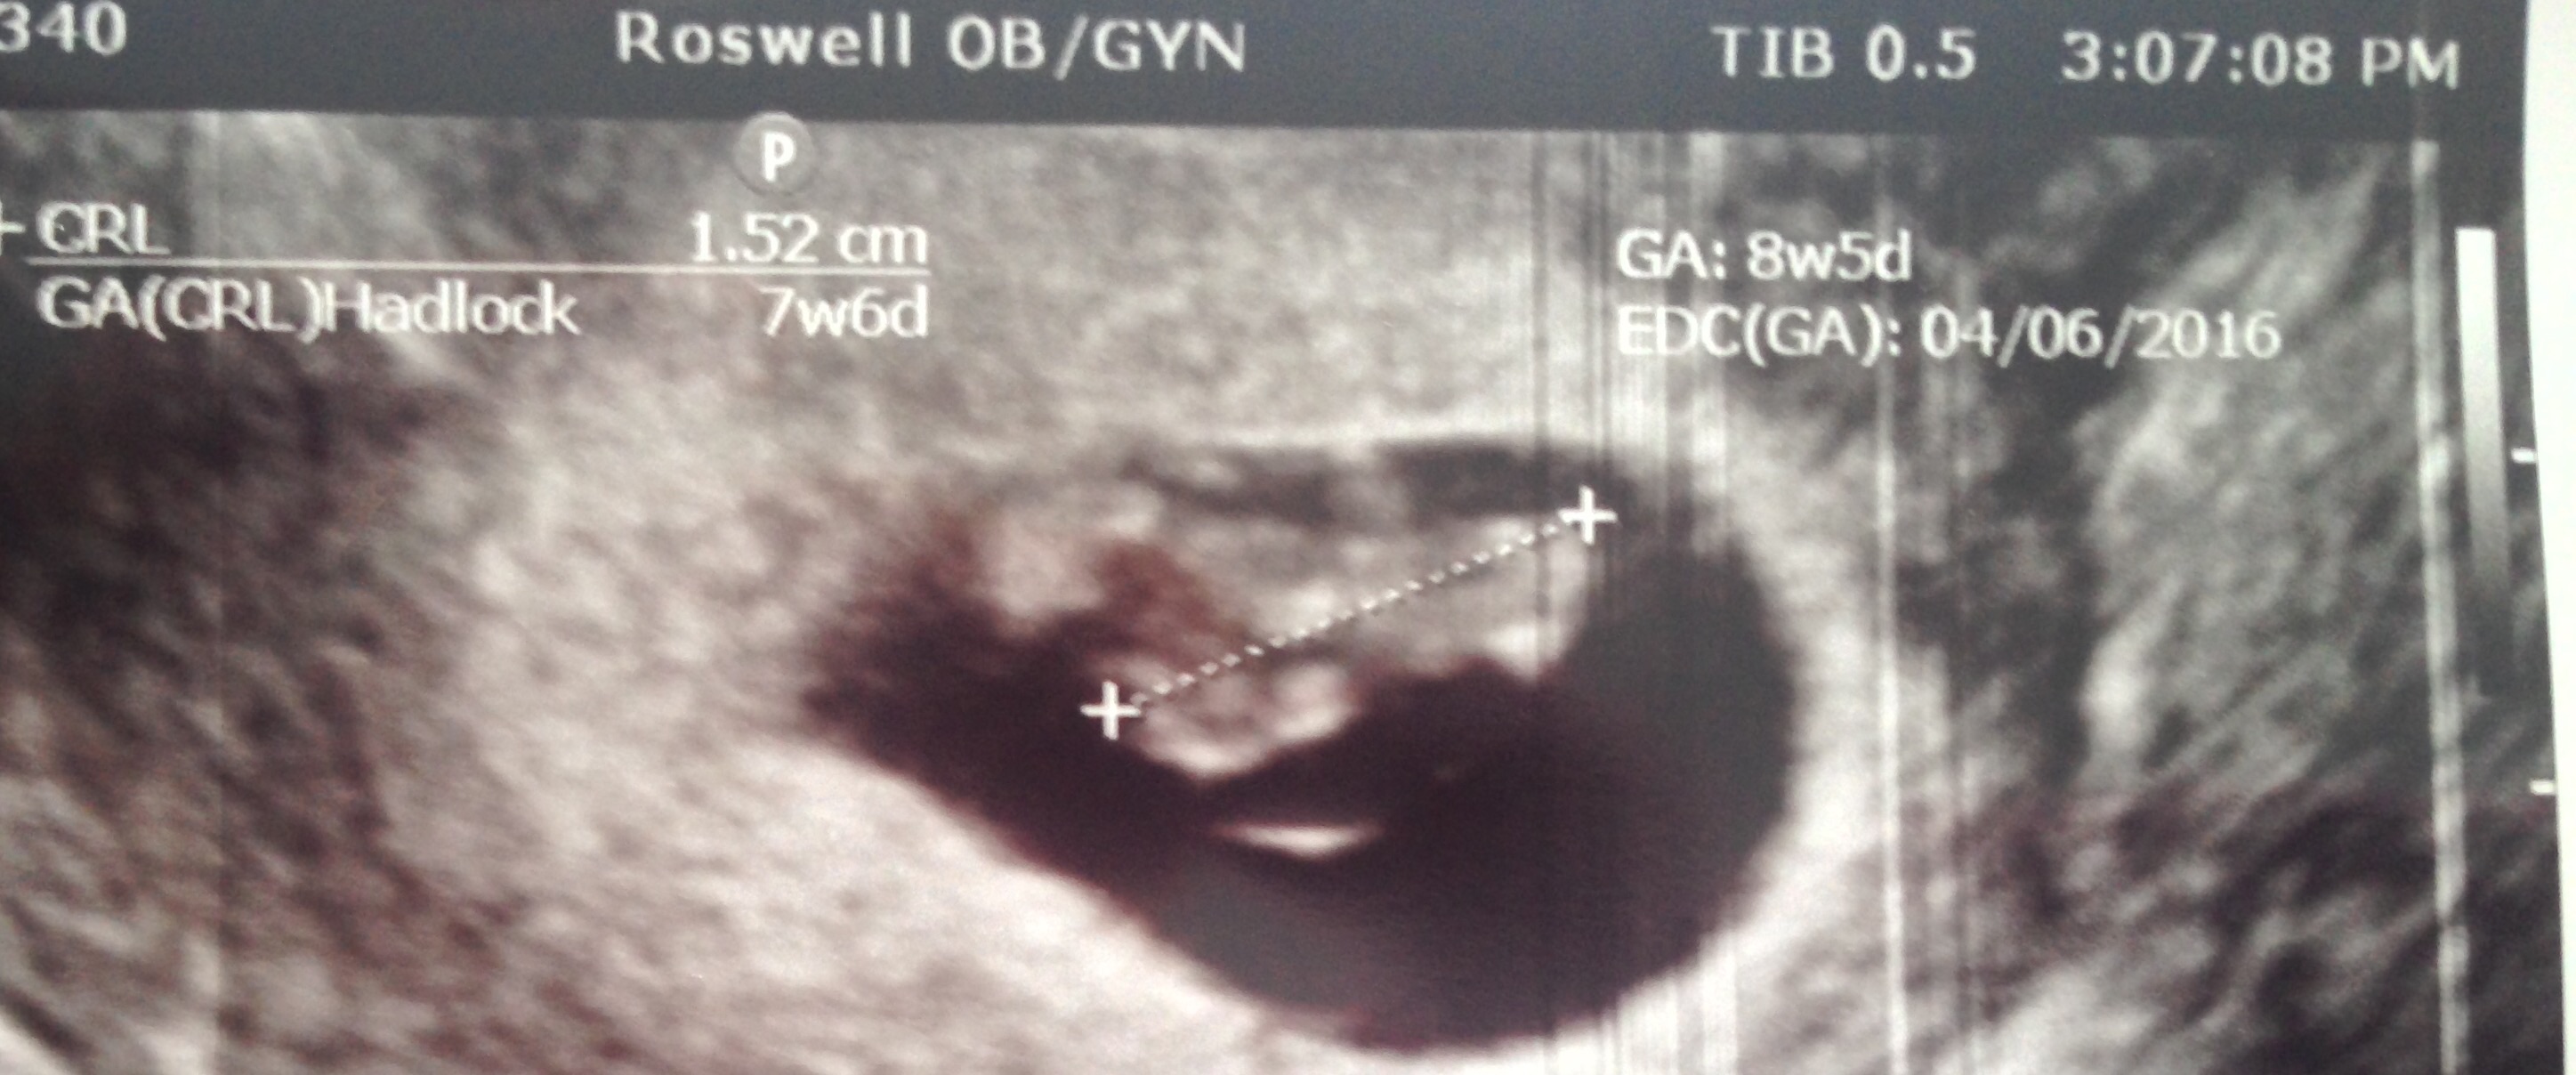

Here is our little Bean! The ultrasound tech thinks the due date is around 4/13/16 (originally thought it was 4/6/16). That puts me at about 7 weeks, 5 days now. Heart rate was 141 and baby measures about 1.5 cm long. We also got to see and hear the heart beat, which is the coolest thing ever!